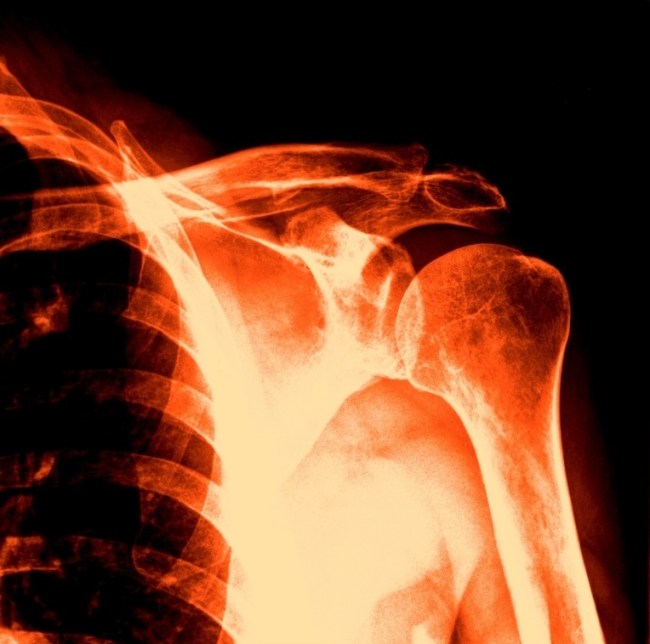

Best of all, the X-ray shoulder views are available, and simple photo-editing software–Paint and Microsoft Office Picture Manager–may be used on the images. Andy Warhol did stuff like this the hard way, back in the day. Longer ago, Robert Rauschenberg had to content himself with light-reactive paper and bright, bright light for some white-on-blue skinscapes of him and his companion. But now–colorizing, brightness&contrast, data compression and many other image-manipulative techniques are easy as pie, funfunfun, and available with the latest operating systems!

So here are four shoulderscapes. If time were not of the essence I would have happily spent another several hours playing with the image; alas, time is scarce. These four, though, demonstrate how color, contrast and cropping of the same subject matter might yield four quite different visual payoffs.